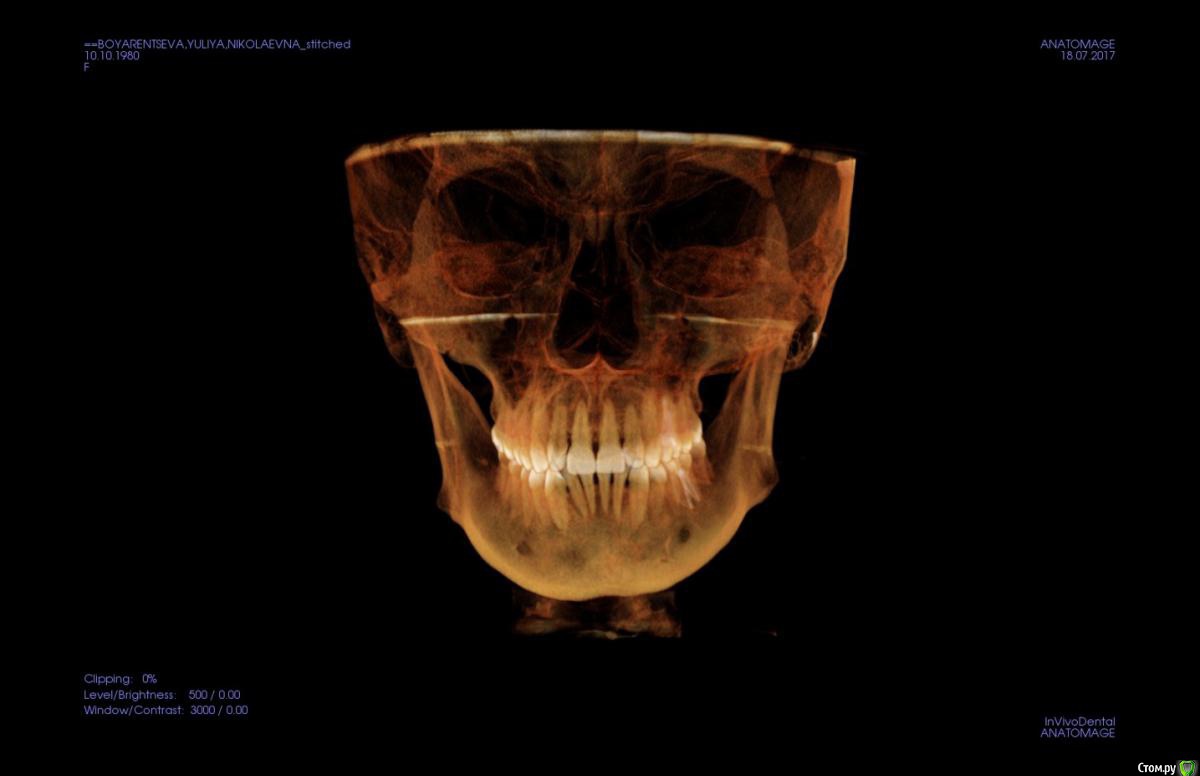

kapyulia Опубликовано 22 декабря, 2017 Поделиться Опубликовано 22 декабря, 2017 Добрый день! Могли бы Вы подсказать есть ли необходимость в удалении зубов (пятерки) с верхней челюсти? Спасибо за помощь. Ссылка на комментарий

Brigita Опубликовано 24 декабря, 2017 Поделиться Опубликовано 24 декабря, 2017 Сложно сказать без очного осмотра, по фото показаний нет. Ссылка на комментарий